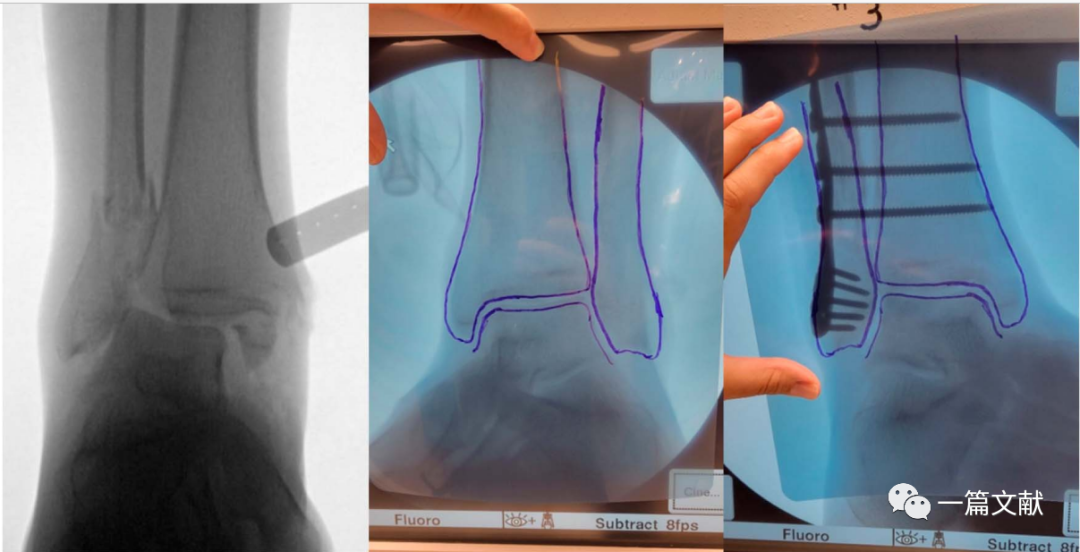

踝关节手术

在患者入手术室后,行无菌铺单前对健侧肢体C臂机透视,并将图像保存于右侧显示屏。若术中需要在垫高状态下进行,则此时应该将健侧肢体垫高透视,尽量做到与术侧肢体一致。当获得满意的正侧位图像后,用薄的描写纸或透明胶片覆盖显示屏图像,并用记号笔对健侧骨骼形态进行临摹。此时我们就获得了患者健侧骨骼轮廓,将其翻转,以此作为标准,对于术中指导和术后检验复位均起重要作用。具体如下图:

上图左侧为健侧标准前后位X片,右侧为临摹的骨骼轮廓。

上图左侧为患侧肢体,中间为临摹的健侧骨骼轮廓。右侧图将临摹后的纸张翻转后贴于C臂机显示屏,作为术中复位模板。术后亦可利用该模板对固定后的骨折进行比对。